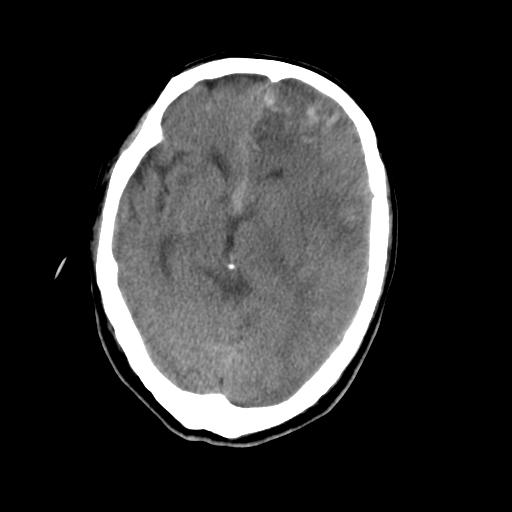

男,78岁。自诉两周前因右侧肢体障碍行ct检查,诊断为脑梗塞(患者ct片已丢失)治疗好转后出院。现因意不清12小时,又行ct检查。

结合病史考虑左侧额颞顶叶出血性脑梗塞。

结合病史考虑左侧额颞顶叶出血性脑梗塞